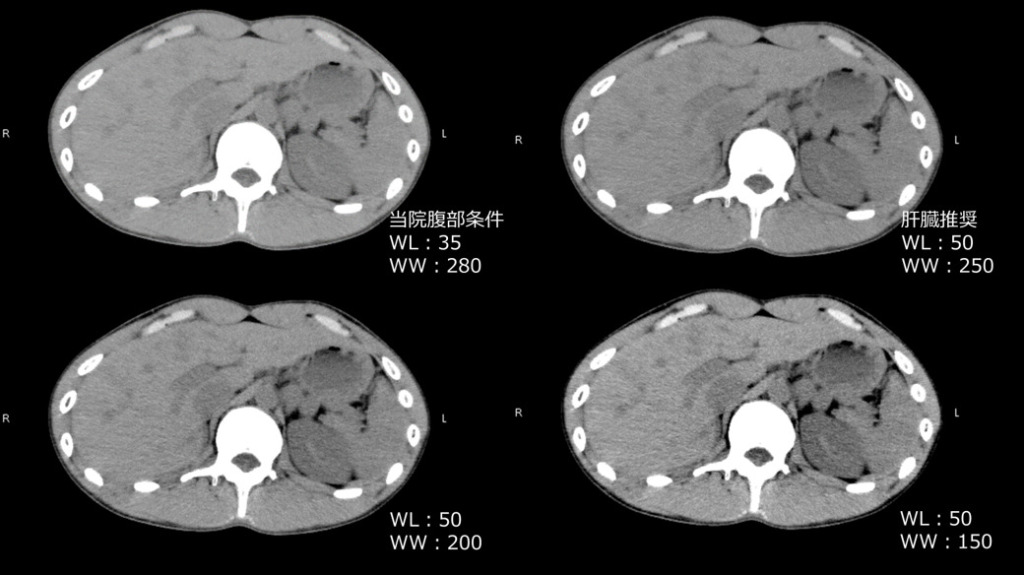

window条件の最適化

わずかな濃度差を見逃さないためには、画像表示条件(ウィンドウ幅:WWとレベル:WL)の調整が不可欠です。肝臓を詳細に観察する場合、通常よりもウィンドウ幅を狭く設定することで、実質内のコントラストが強調され、損傷部位が浮き彫りになりやすくなります。

左上の表は当院のwindow条件です。

胸腹部CTのウィンドウ条件はWW300、WL25で表示してます。

右上の画像がそれにあたります。本症例の画像がこのウィンドウ条件です。

腹部だけの撮影の場合は、WW280、WL35で表示してます。

X線CT撮像ガイドライン(GALACTIC)によると

腹部撮影ではWW300程度、WL50程度、肝臓病変の撮影ではWW250程度、WL50程度を推奨されています。

右下の画像がWW250程度、WL50程度にあたります。

また、肝臓のみを観察する時はWWを200程度と狭めにすると肝病変のコントラストがつきやすいとのことでした。

左上は当院の腹部のW条件

右上はGALACTICの肝病変ターゲット時の腹部全体推奨されてるwindow条件、

左下はGALACTICの肝臓のみの観察時に推奨されてるWW200、右下はさらにWWを150と狭めてます。

左上の画像は肝内のコントラストがはっきりしない様に見えますが、WWを狭くすることでCT値のわずかな差が強調され、肝内のコントラストが強くなり、臓器の輪郭や出血を観察しやすくなります。

まずはWWが広い画像で全体像を観察し、その後臓器にあわせてwindow条件を調節して観察することも大切になります。